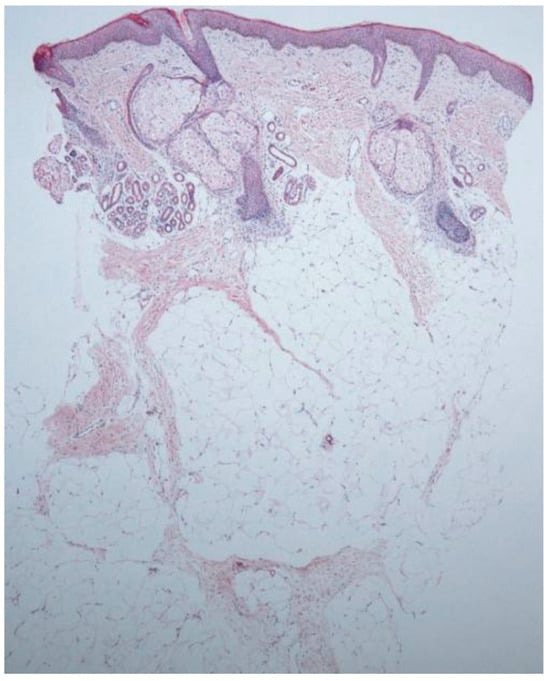

Melanoma is a highly aggressive skin cancer primarily linked to ultraviolet (UV) radiation. However, the potential role of ionizing radiation from radiotherapy in melanoma development remains unclear. This review synthesizes data from epidemiologic s...